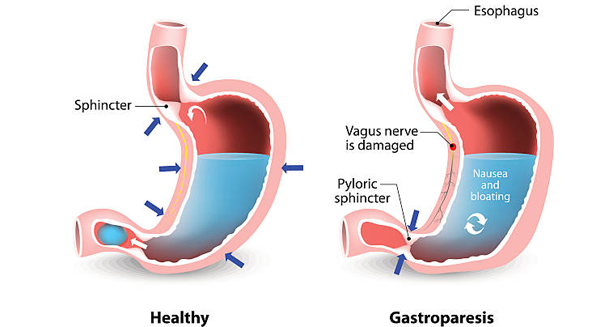

Gastroparesis occurs when the stomach’s normal muscle or nerve function becomes disrupted, preventing food from moving efficiently through the digestive tract. This dysfunction stems from various underlying conditions, each affecting the digestive system in different ways.

Among all known causes, diabetes stands out as the most common contributor to gastroparesis. Over time, persistently high blood sugar levels can damage the vagus nerve, which plays a crucial role in triggering the stomach’s muscle contractions. As the nerve weakens, stomach motility slows down significantly.

Certain surgical procedures can inadvertently damage the nerves responsible for stomach function. For example, operations involving the stomach, oesophagus, or adjacent organs may lead to gastroparesis if nerves such as the vagus nerve are affected.